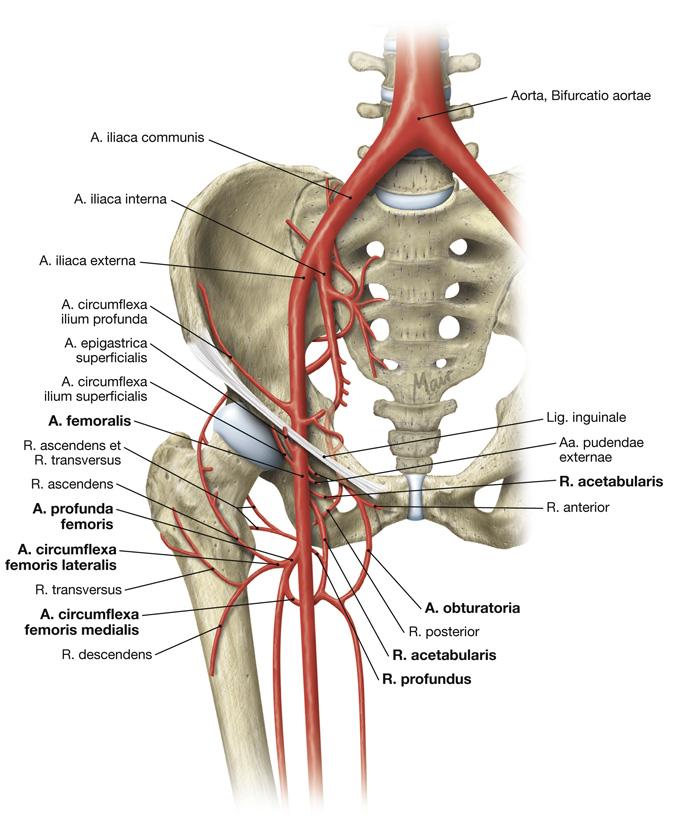

Fig 3.30: a. iliaca externa

Sobotta: Fig 4.155